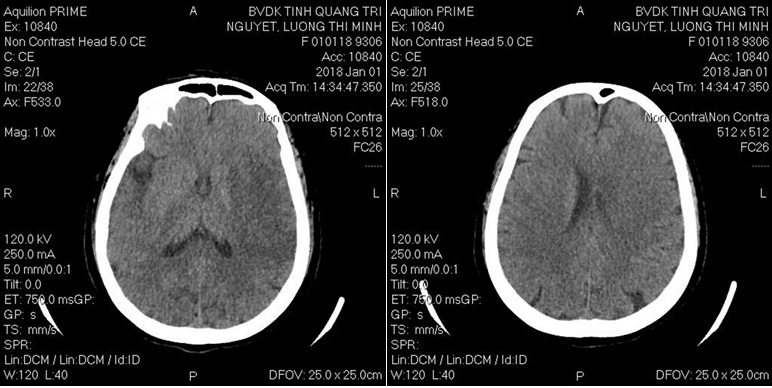

+ Chụp CTSN không tiêm CQTM sọ chưa thấy hình ảnh bất thường

Hình: CTVT sọ não sau 2 ngày lấy huyết khối